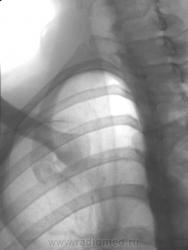

Молодая женшина. 31 год. На плановой цифровой ФГ выявлено неясного генеза изменения. При контрольной прицельной рентгенографии - в правой ключице. Чем Вы можете обьяснить локальный остеосклероз грудинного конца ключицы? При изучении анамнеза - отмечает боль в ключице (соответствует выявленым изменениям), которая распространяется на плечо, надплечье, спину и ...даже в правую руку... Рекомендована КТ.

Виктор Григорьевич, очень тщательно смотришь, забросаешь себя контролями, не отобьешся. Склероз для кости - это не плохо, это не деструкция... Нужно посмотреть, что там в шее (по симптомокомплексу)

А может это синдром Титце...

Была и у меня схожая мысль...но сбивает с толку остеосклероз....

Также нельзя исключить костную мозоль на почве перелома ребра, болезненные метастазы злокачественных опухолей или первичную опухоль ребра. В клинике крови есть какие-либо изменения?